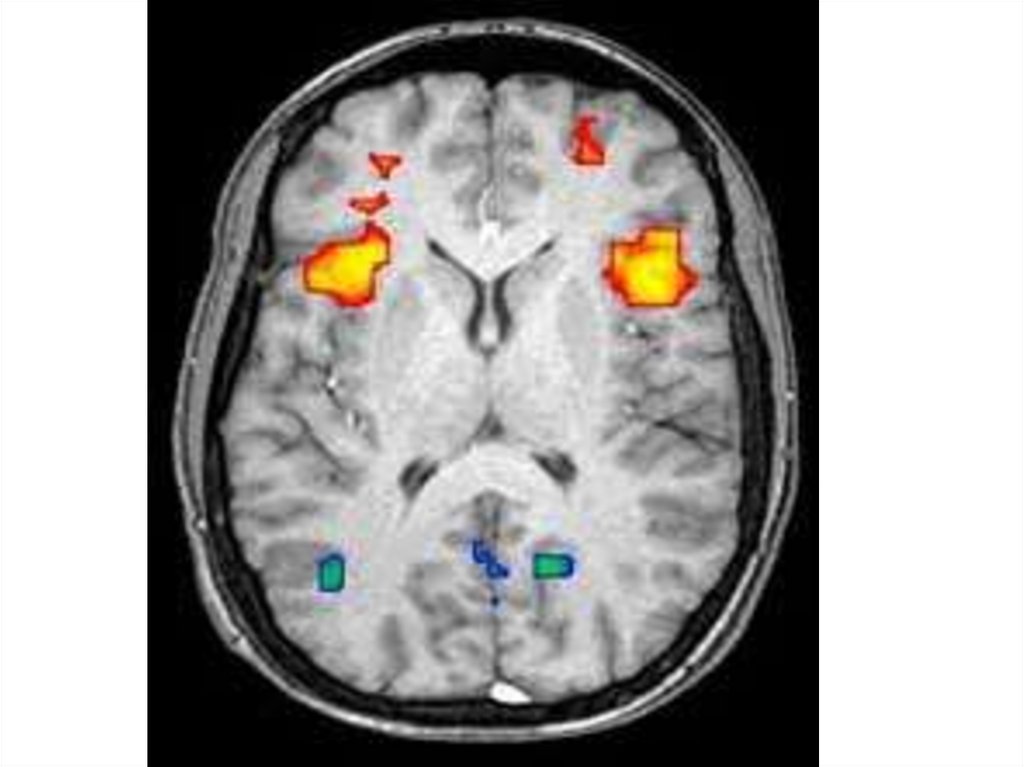

Анатомия аутизма